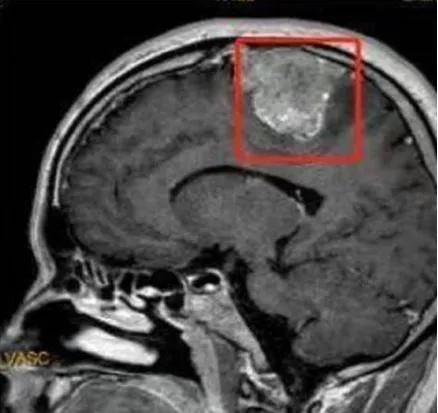

腦腫瘤

惡性神經膠質母細胞瘤

膠質母細胞瘤